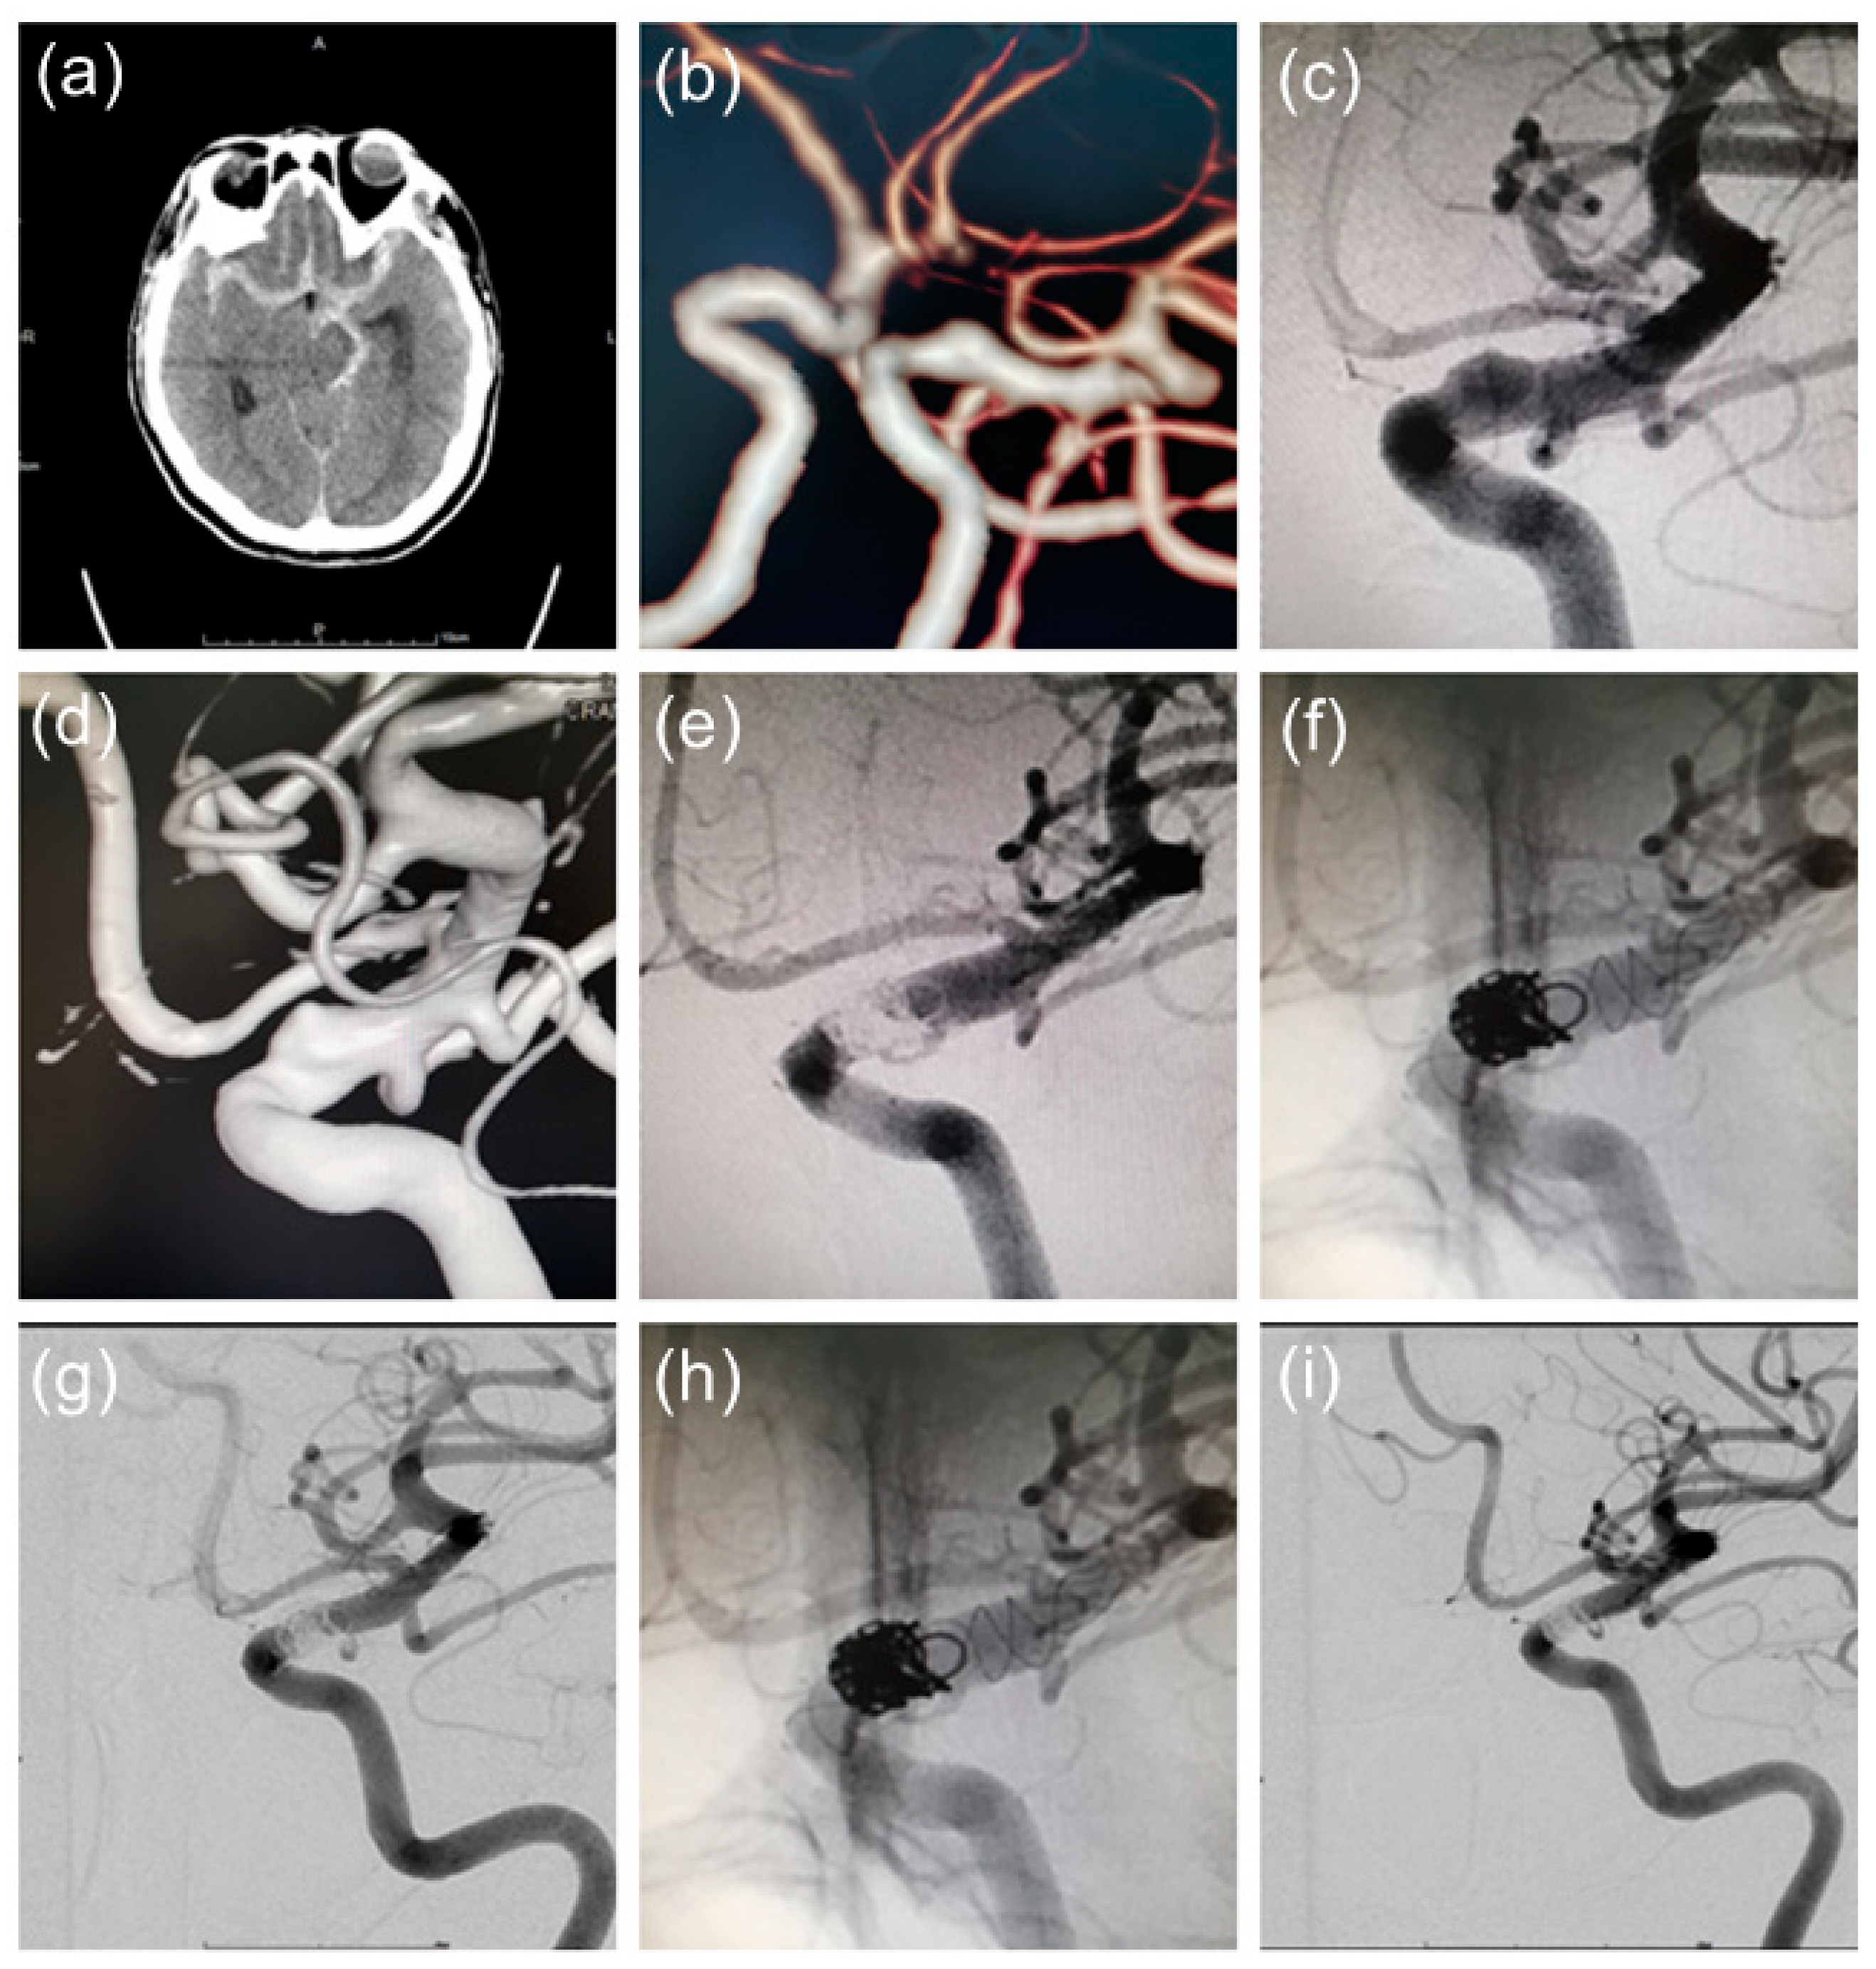

4. Typical Case